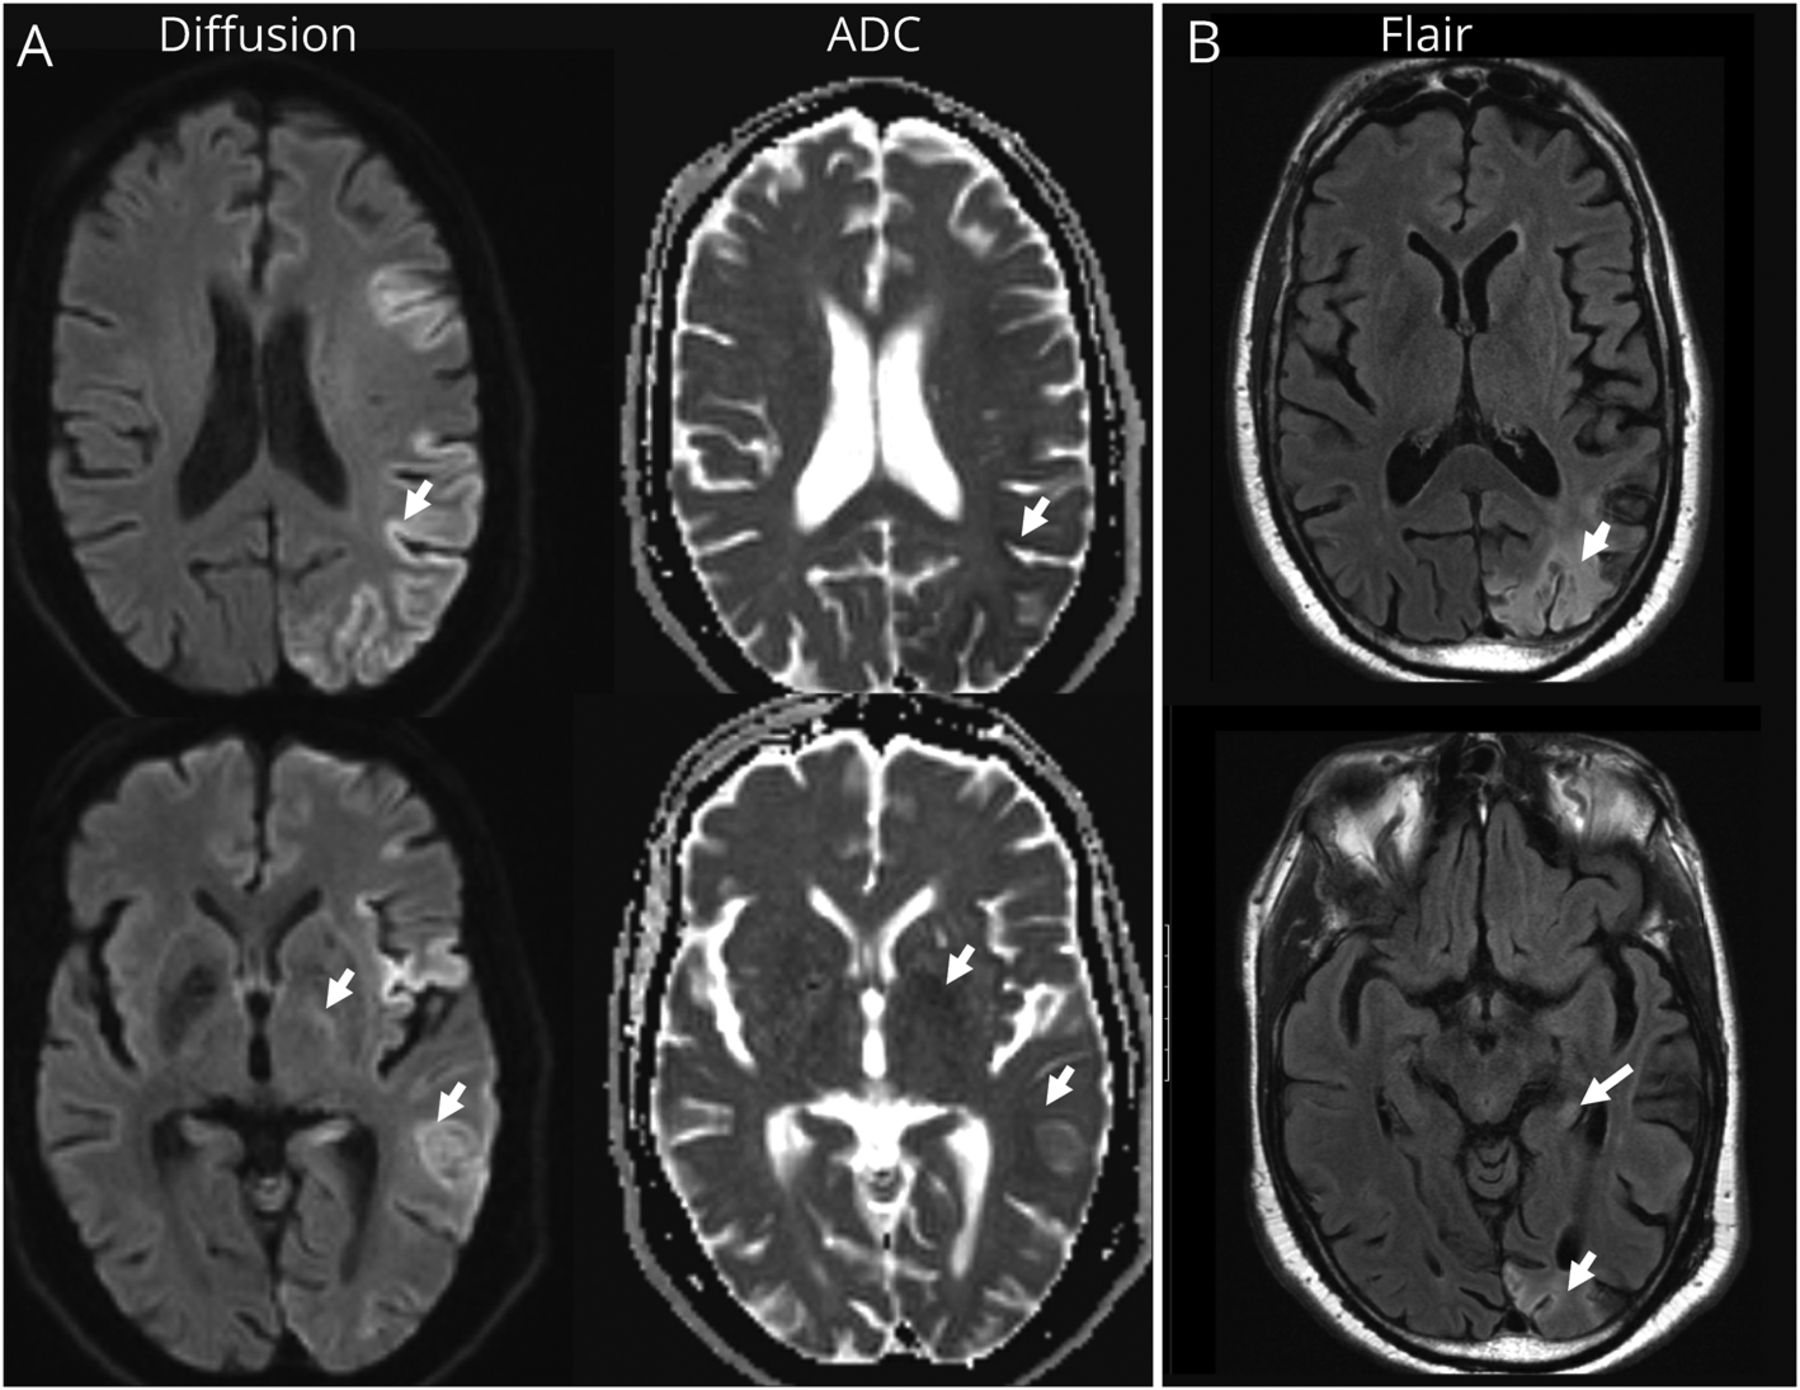

一名62岁的男性在车祸后表现出困惑、激动和压力,说话切线。脑MRI显示左半球皮层带状化,提示脑炎、癫痫或朊病毒病(图)。4天脑电图显示左半球减慢,但没有癫痫样活动。毒理学和感染性检查均为阴性。脑脊液抗nmda受体抗体阳性。肿瘤评估没有揭示什么。患者接受了5天的甲基强的松龙静脉注射和IVIG,注意力改善,能够遵从命令,并参与适当的谈话。抗nmda受体脑炎常发生于年轻女性患者1,2通常与畸胎瘤有关。虽然通常是正常的,但如果大脑MRI检查结果存在,病变更常报告在内侧颞叶。本病例表明,急性至亚急性精神状态改变伴非典型MRI发现单侧皮质带状病变可能是抗nmda受体脑炎的表现。识别这种非典型表现对于早期治疗和最大程度的功能恢复很重要。⇓